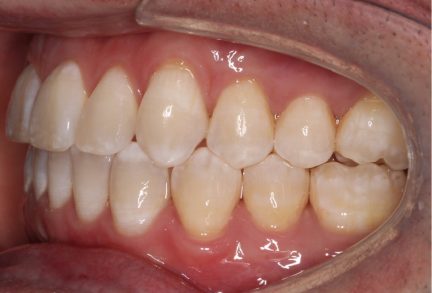

État initial

État final